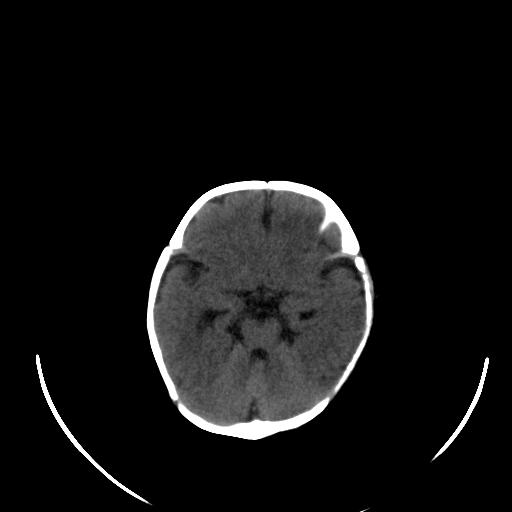

患儿 女性 1个月  今天发现阵发性抽搐  双眼上翻、凝视,嘴唇及面色青紫

考虑双侧脉络膜裂囊肿。

双侧颞枕叶片状低密度影,考虑新生儿却血缺氧性脑病可能

左侧额叶见班片样低密度灶,症状像癫痫,可能与之有关。

新生儿却血缺氧性脑病不排除!

左侧额叶见班片样低密度灶,建议mr

考虑hie。

考虑新生儿hie。